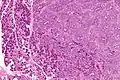

This tumour is characterised by biphasic tubular structures composed of inner ductal and outer clear myoepithelial cells.

The histologic differential diagnosis includes adenoid cystic carcinoma and pleomorphic adenoma.

Intermed. mag.